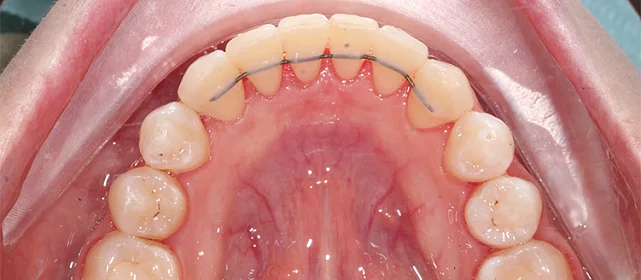

Прозрачные элайнеры Click на обе челюсти. Расширить зубные дуги, убрать скученность, выровнять линию смыкания. Основной набор — 32 капы. Срок — около 2 лет.

Лечение заняло 30 месяцев (август 2023 — февраль 2026). Понадобились три дополнительных набора: 30, 10 и 10 кап — итого 82 капы. Пациентка живёт за рубежом, приезжала на визиты — что иногда влияло на частоту контроля и сроки. На ретенцию приехала отдельно.

Решение: Поставили элайнеры Click на обе челюсти. Начали с 32 кап, но случай потребовал три дозаказа: 30, 10 и 10 кап — итого 82 капы за 30 месяцев. Количество дозаказов объясняется и сложностью случая (скученность плюс деформация кривой Шпее), и тем, что контрольные визиты были реже обычного из-за проживания за границей. Тем не менее результат достигнут: зубы ровные, смыкание в норме. На ретенцию пациентка приехала отдельно — зафиксировали ретейнеры на обе челюсти, сняли слепки для ретенционных кап.

Сложный случай: скученность на обеих челюстях плюс деформация кривой Шпее — жевательные зубы на разной высоте. Дополнительный вызов — пациентка живёт за рубежом, визиты реже, контроль сложнее. Три дозаказа — много, но каждый был обоснован: основной набор расширил дуги и убрал основную скученность, дозаказы последовательно довели смыкание до нормы. 82 капы за 30 месяцев — результат получен.